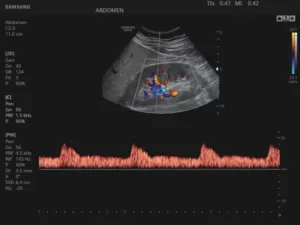

Режим PW (Pulsed Wave, спектральный, или импульсно-волновой)

В данном режиме ультразвук испускается сериями им­пульсов, которые, отразившись от эритроцитов, последовательно принимаются этим же датчиком. Также имеется воз­можность избирательного измерения скорости кровотока в отдельном сосуде.

Минусами PW-доплерографии являются невозможность исследования высоких скоростей потока в сосу­дах, расположенных на большой глубине, и вероятность искажения спектра скоростей течения жидкости, когда высокоскоростной кровоток ошибочно отображается как низко­скоростной.

28.jpg

Рис.4. Сердце плода в PW-режиме.